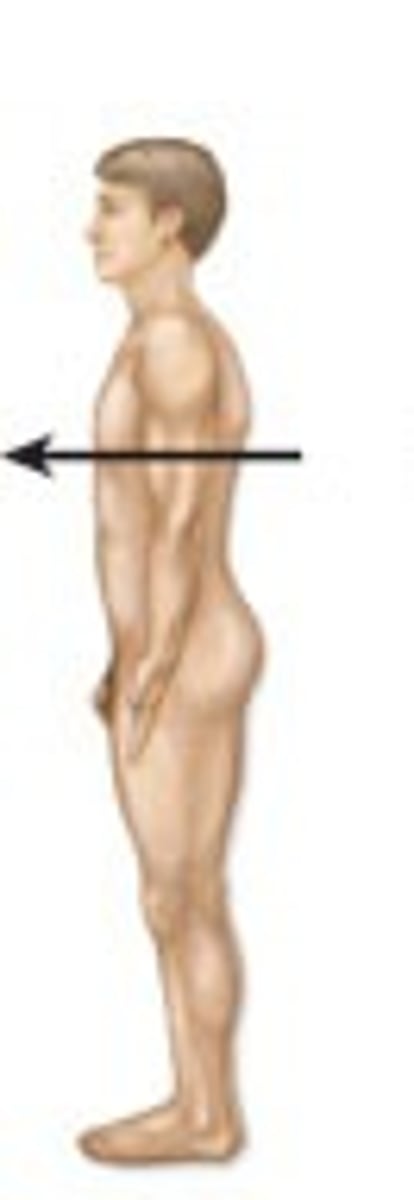

Ventral

Toward the belly

Dorsal

Toward the back